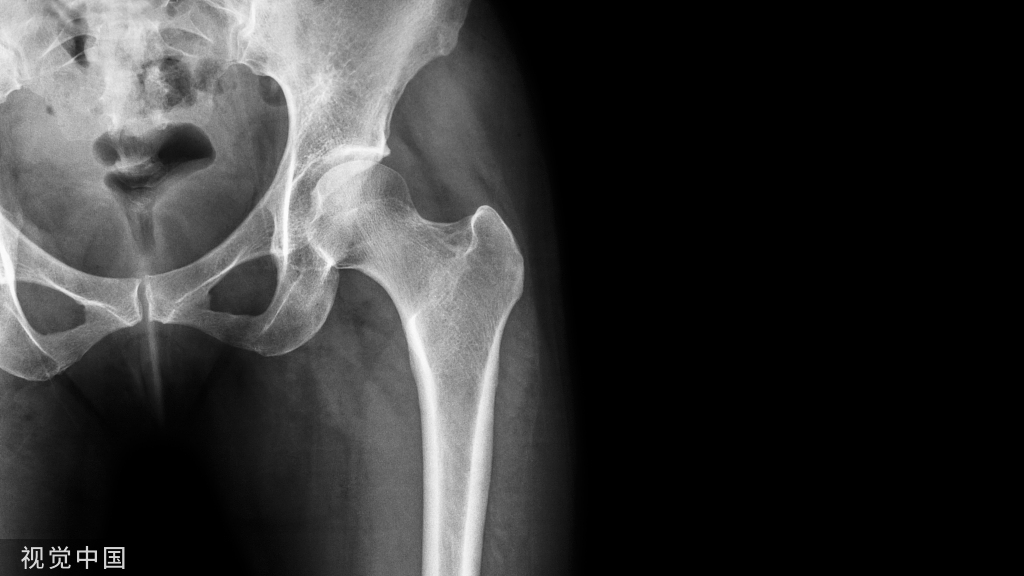

随着人类寿命的延长和老龄化社会的到来,骨质疏松发病率逐年增加,已成为人类的重要公共健康问题。骨质疏松患者在使用抗骨质疏松药物的同时,还要根据维生素 D 水平决定是否需要补充维生素 D。

由于维生素 D3 和维生素 D2 是骨骼代谢的重要物质,能够促进小肠对钙的吸收并促使骨骼的形成,所以说晒太阳能补充维生素 D,还可以补钙,预防和改善骨质疏松。